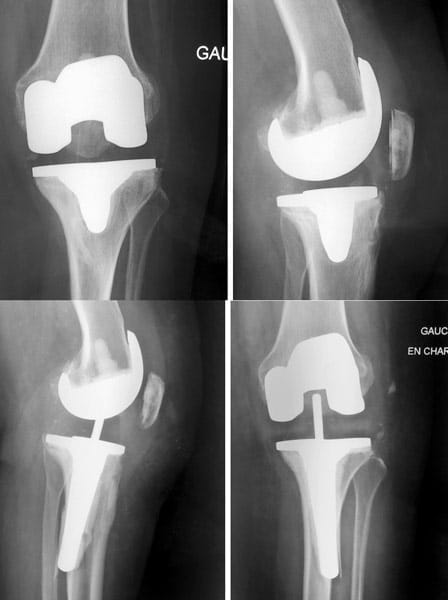

Femme de 88 ans, opérée par prothèse totale du genou NexGen à droite il y a 19 ans et à gauche il y a 18 ans.

Aucune douleur, aucune usure.

La courbe de survie de la prothèse NexGen dans les registres Australien et Anglais est de 98% à 11 ans de recul.